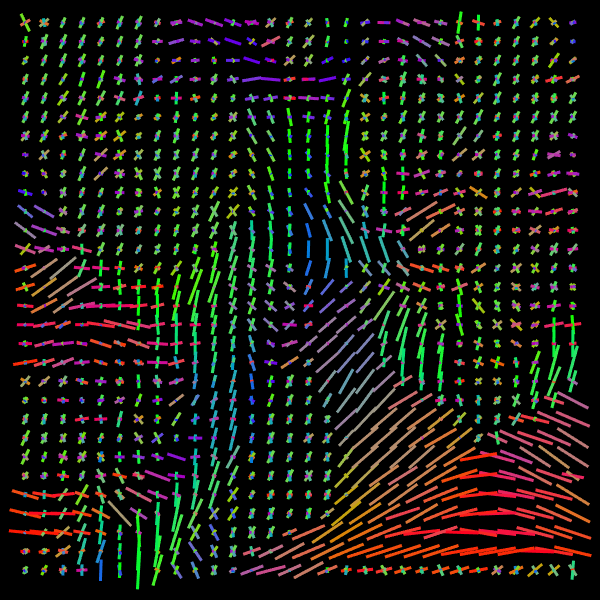

Training stage. We compare the results of the proposed Voxel (VOX) and Neighborhood (NBH) models with two of the SOTA methods which tackle the same task: Diffusion Basis Functions (NNLS) proposed by Ramirez-Manzanares et al. (2007)) and Constrained Spherical Deconvolution (CSD) proposed by Tournier et al. (2007). There are many options to compare distributions, a common comparisson procedure used in this context is to detect peaks and compute the angular error between the real peaks and the estimated ones. However, to compare modes in not a standard procedure for comparing distributions. Among them two notable options are Kullback-Leibler (KL) Divergence and the Wasserstein Distance (also know as the Earth Mover Distance, EMD). Despite its computational cost, EMD has shown to represents more precisely the distribution distance (Levina and Bickel, 2001; Aranda et al., 2011; Arjovsky et al., 2017). EMD represents the minimum cost of transforming a peak distribution into another, weighting by angle. We create a synthetic dataset with gradient table of the Stanford HARDI dataset (Rokem et al., 2015), the eigenvalues of a Diffusion Tensor model fitted to the corpus callosum region, and the SNR computed in such a data (Descoteaux et al., 2011). The estimated SNR depends on image region: most of the measures laid into [20,24]2024[20,24], so we randomly generate data selecting the SNR into [20,30]2030[20,30]. Figure 5 depicts the error for each analyzed model. The vertical axis corresponds to the angle (θ1subscript𝜃1\theta_{1}) between the first PDD and the second one. Meanwhile, the horizontal axis shows the angle between the third PDD and the plane formed by the first two PDDs. The dynamic range of the error maps shows a better performance of the proposed models. We select some predictions for a visual inspection (qualitatively comparison). For illustration purposes, we choose one between the top–101010 and one of the bottom–101010 according to its EMD values for the studied models: VOX, NBH, NNLS, and CSD. The results are presented in Figure 6. The first two columns correspond to the best predictions: the first column shows the target and the second column shows the prediction. The third and fourth columns follow the same order but for the worst predictions. Arrows illustrate the generated PDDs (ground truth). According to the α𝛼\alpha value: blue, orange, and green were used for the first, second, and third PDD, respectively.

Refer to caption

Figure 5: EMD (error) heat-maps by model predictions.